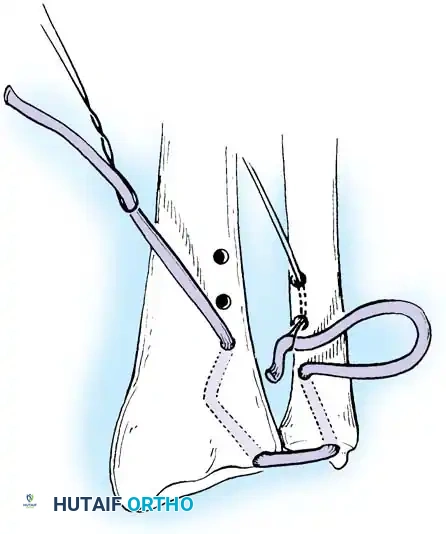

The sutures are tied securely over the cortical bone bridge of the ulnar neck, restoring tension to the radioulnar ligaments.

- Tie the sutures over the ulnar cortical bridge with the forearm in neutral rotation to restore anatomic tension.

In cases of severe instability or concomitant ECU subsheath disruption, open capsular repair and ECU stabilization are required.

Open repair of the dorsal capsule and TFCC, ensuring robust closure and stabilization of the ulnar-sided structures.

Stabilization of the ECU tendon and subsheath, a critical step in addressing complex ulnar-sided wrist trauma.